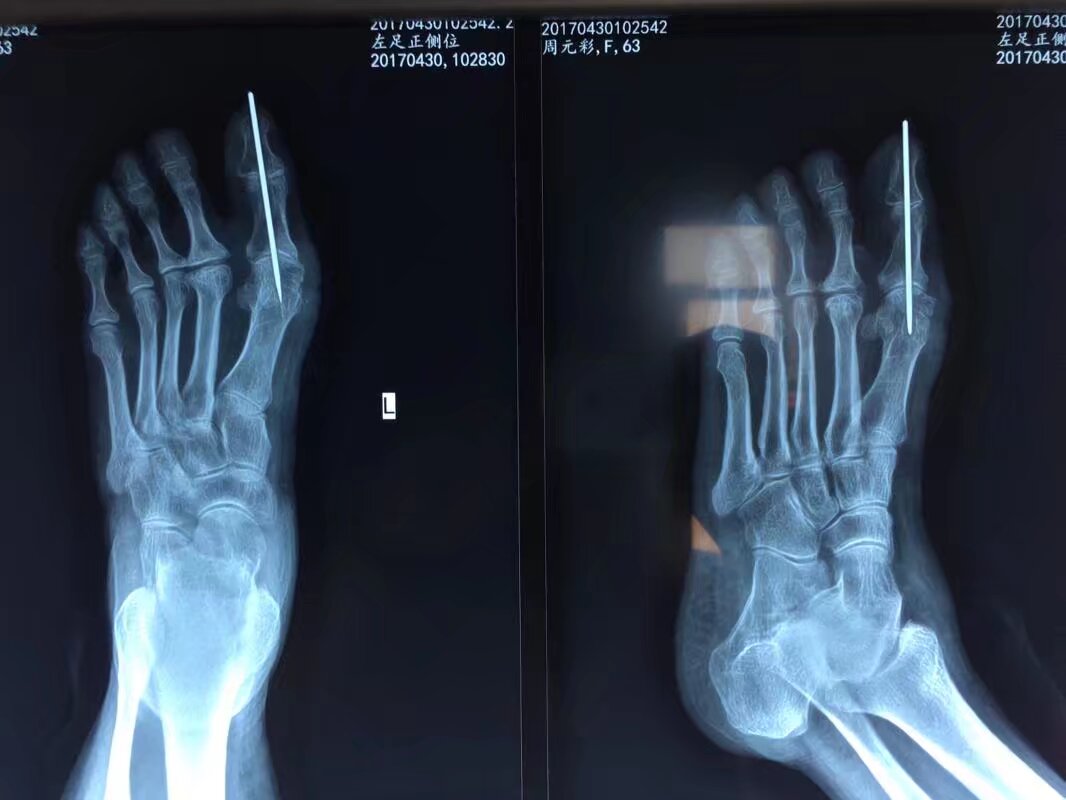

指骨骨折后,克氏针固定是临床常用的治疗方法,尤其适用于手法复位困难或不稳定的骨折,其应用主要体现在以下方面:

2常用固定方式

- 单根克氏针固定:适用于简单横形骨折或斜形骨折,从骨折一端穿入,穿过骨折线至另一端,直接固定断端。

- 交叉克氏针固定:对于斜形、螺旋形或粉碎性骨折,采用两根克氏针交叉穿入骨折端,增加固定稳定性,防止旋转或侧方移位。

- 髓腔内固定:从指骨远端或近端髓腔穿入克氏针,贯穿骨折线,利用髓腔支撑作用固定,适用于长斜形或短缩倾向明显的骨折。

3术后注意事项

- 适时拔除克氏针:一般固定4-6周,根据骨折愈合情况(通过X线检查确认)拆除,避免长期固定导致关节僵硬。